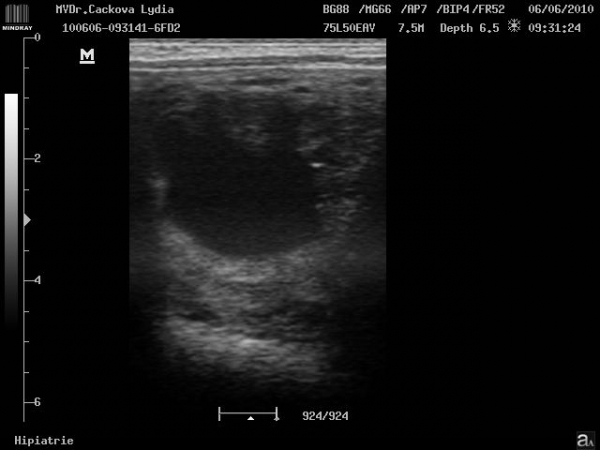

ultrasonografické vyšetření klisny

embryo kolem 21.dne